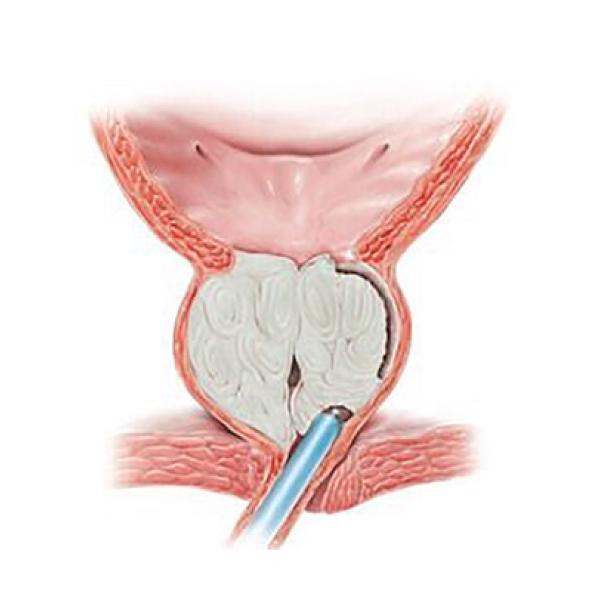

Лікування:. Оперативне: Бужування мембранозного відділу уретри під моніторним контролем, висічення гнійно-сечової нориці промежини, біопсія тканин промежини від 28.09.06. Гістологічне заключення №30313-16 від 2.11.06 р. – плоскоклітинний неороговіваючий Сг із Сг клітинами в судинах.

Лікування:. Оперативне: Бужування мембранозного відділу уретри під моніторним контролем, висічення гнійно-сечової нориці промежини, біопсія тканин промежини від 28.09.06. Гістологічне заключення №30313-16 від 2.11.06 р. – плоскоклітинний неороговіваючий Сг із Сг клітинами в судинах.